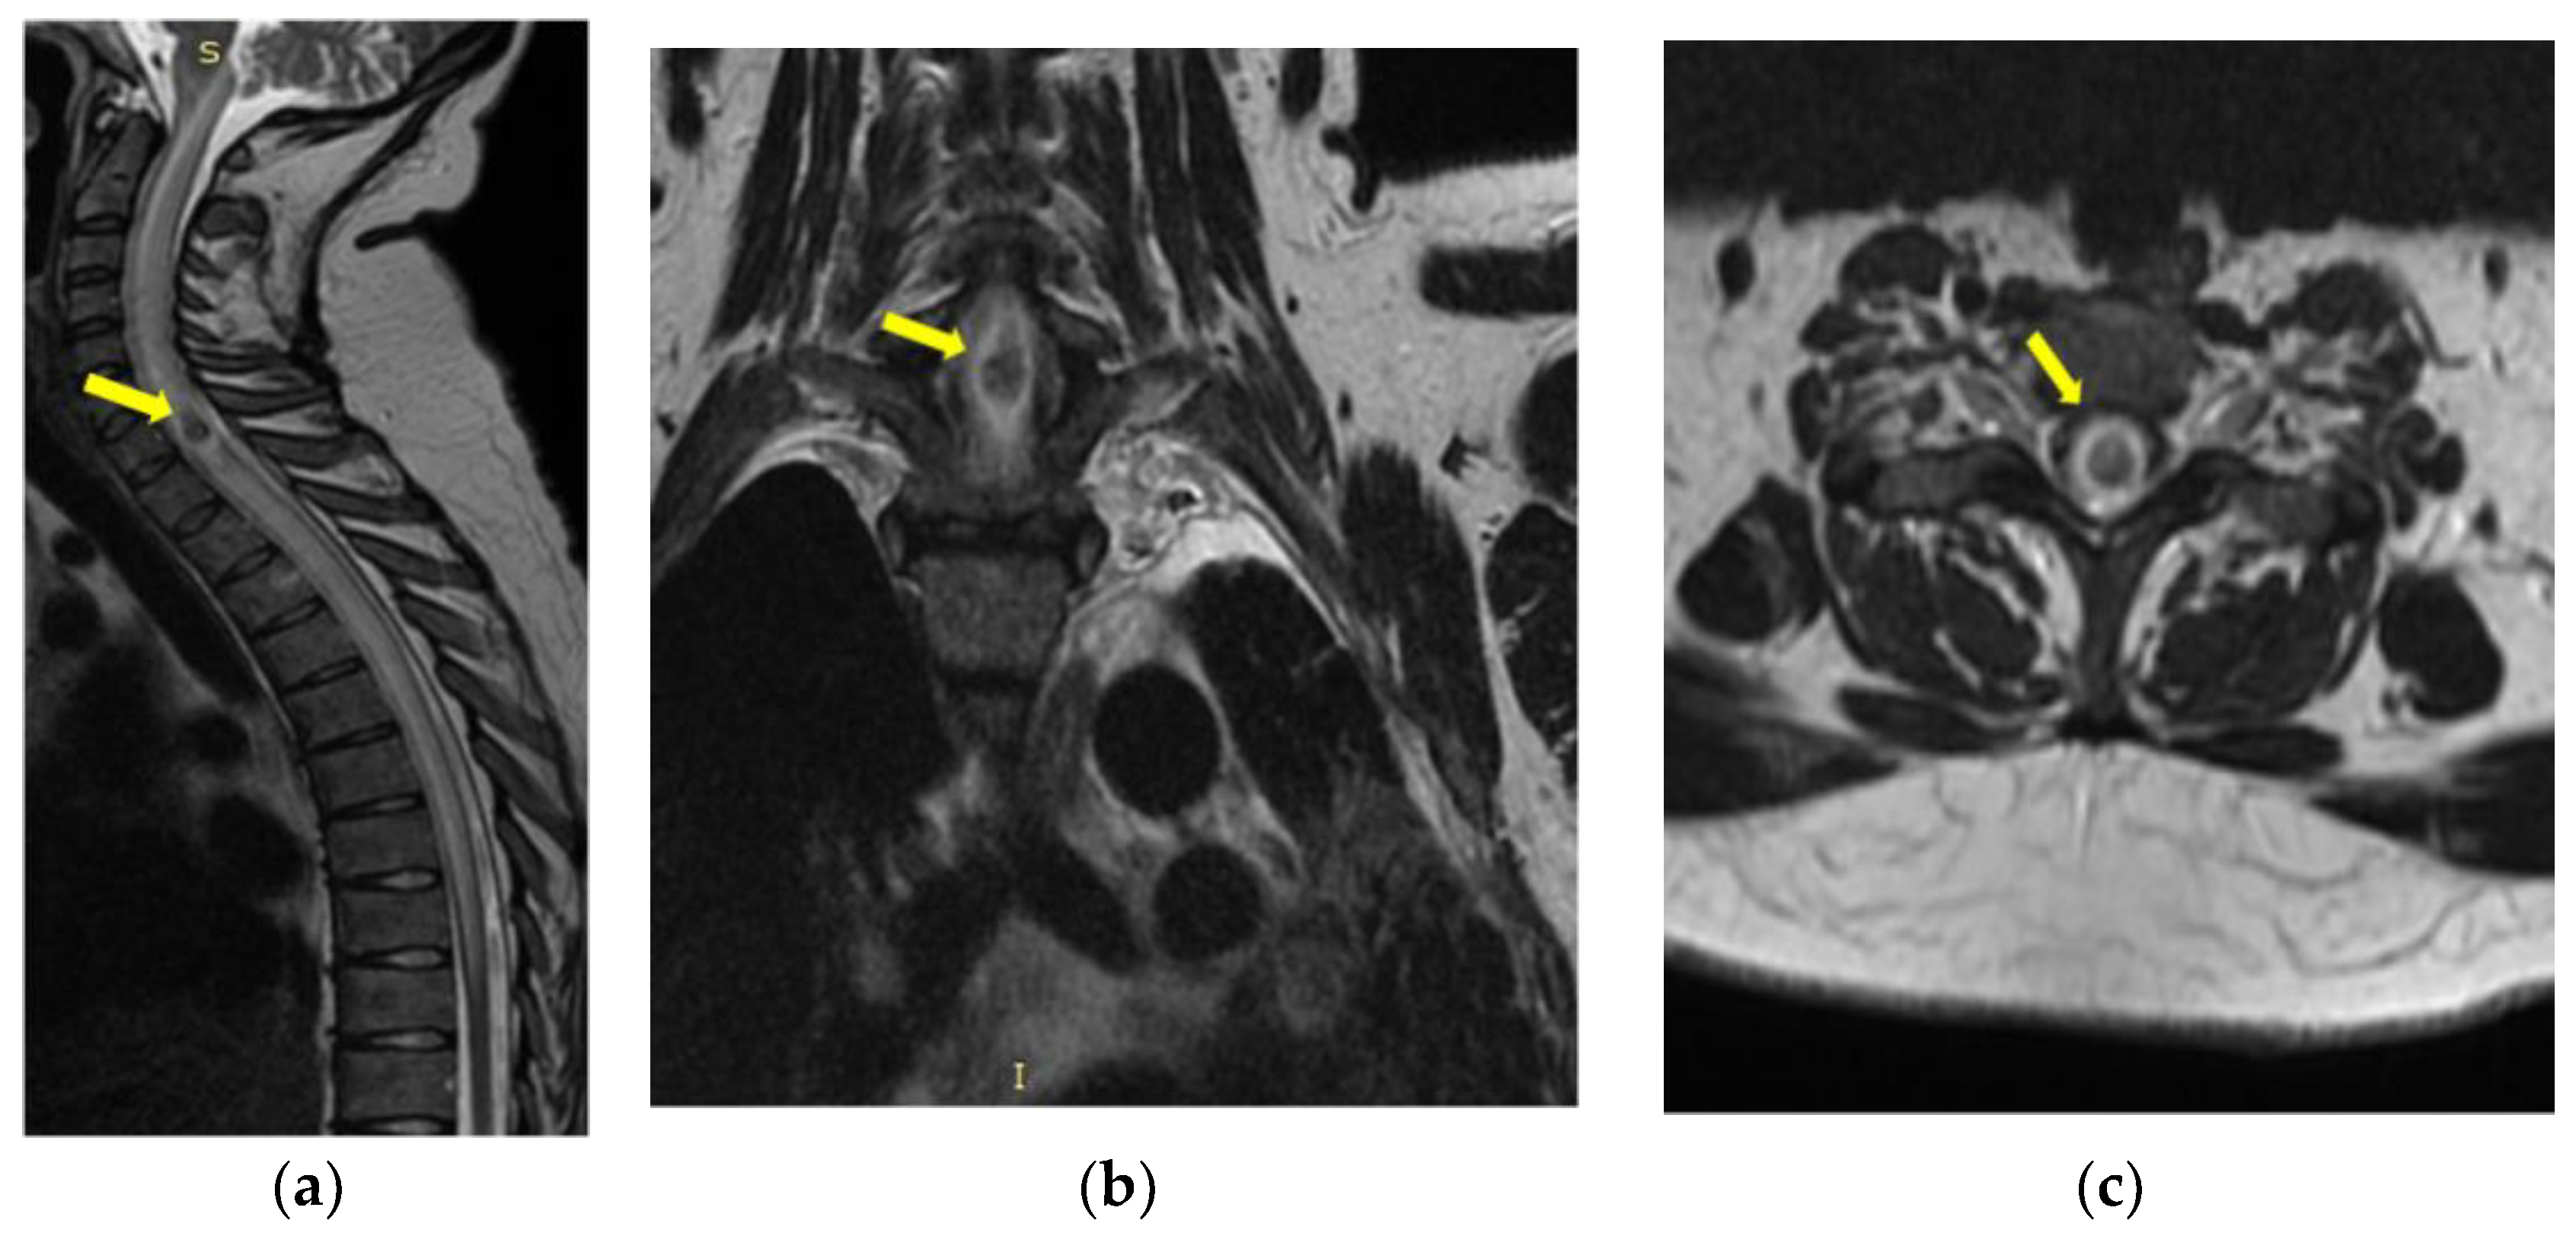

- Mycological demonstration of Aspergillus fumigates hyphae by microscopy from spu-tum, microscopy and culture from bronchial aspirate, and histopathological evi-dence of the presence of Aspergillus fumigates hyphae with dichotomous branching in the spinal cord biopsy;